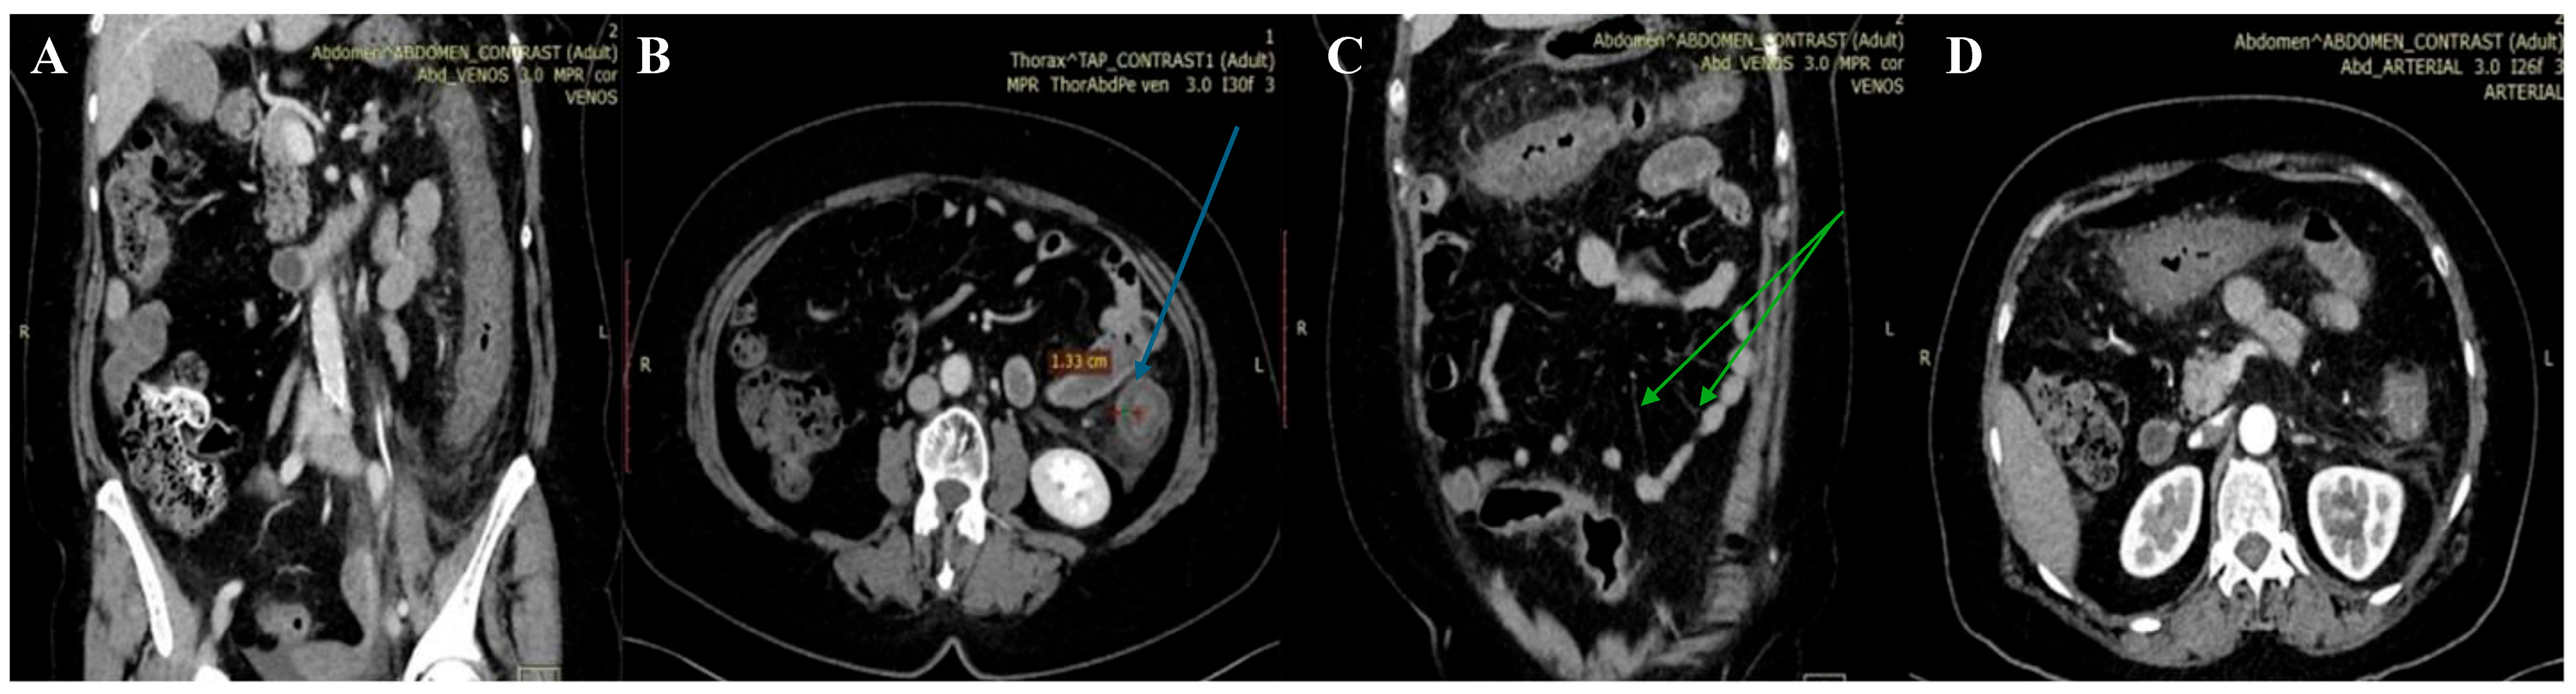

2. Case Presentation